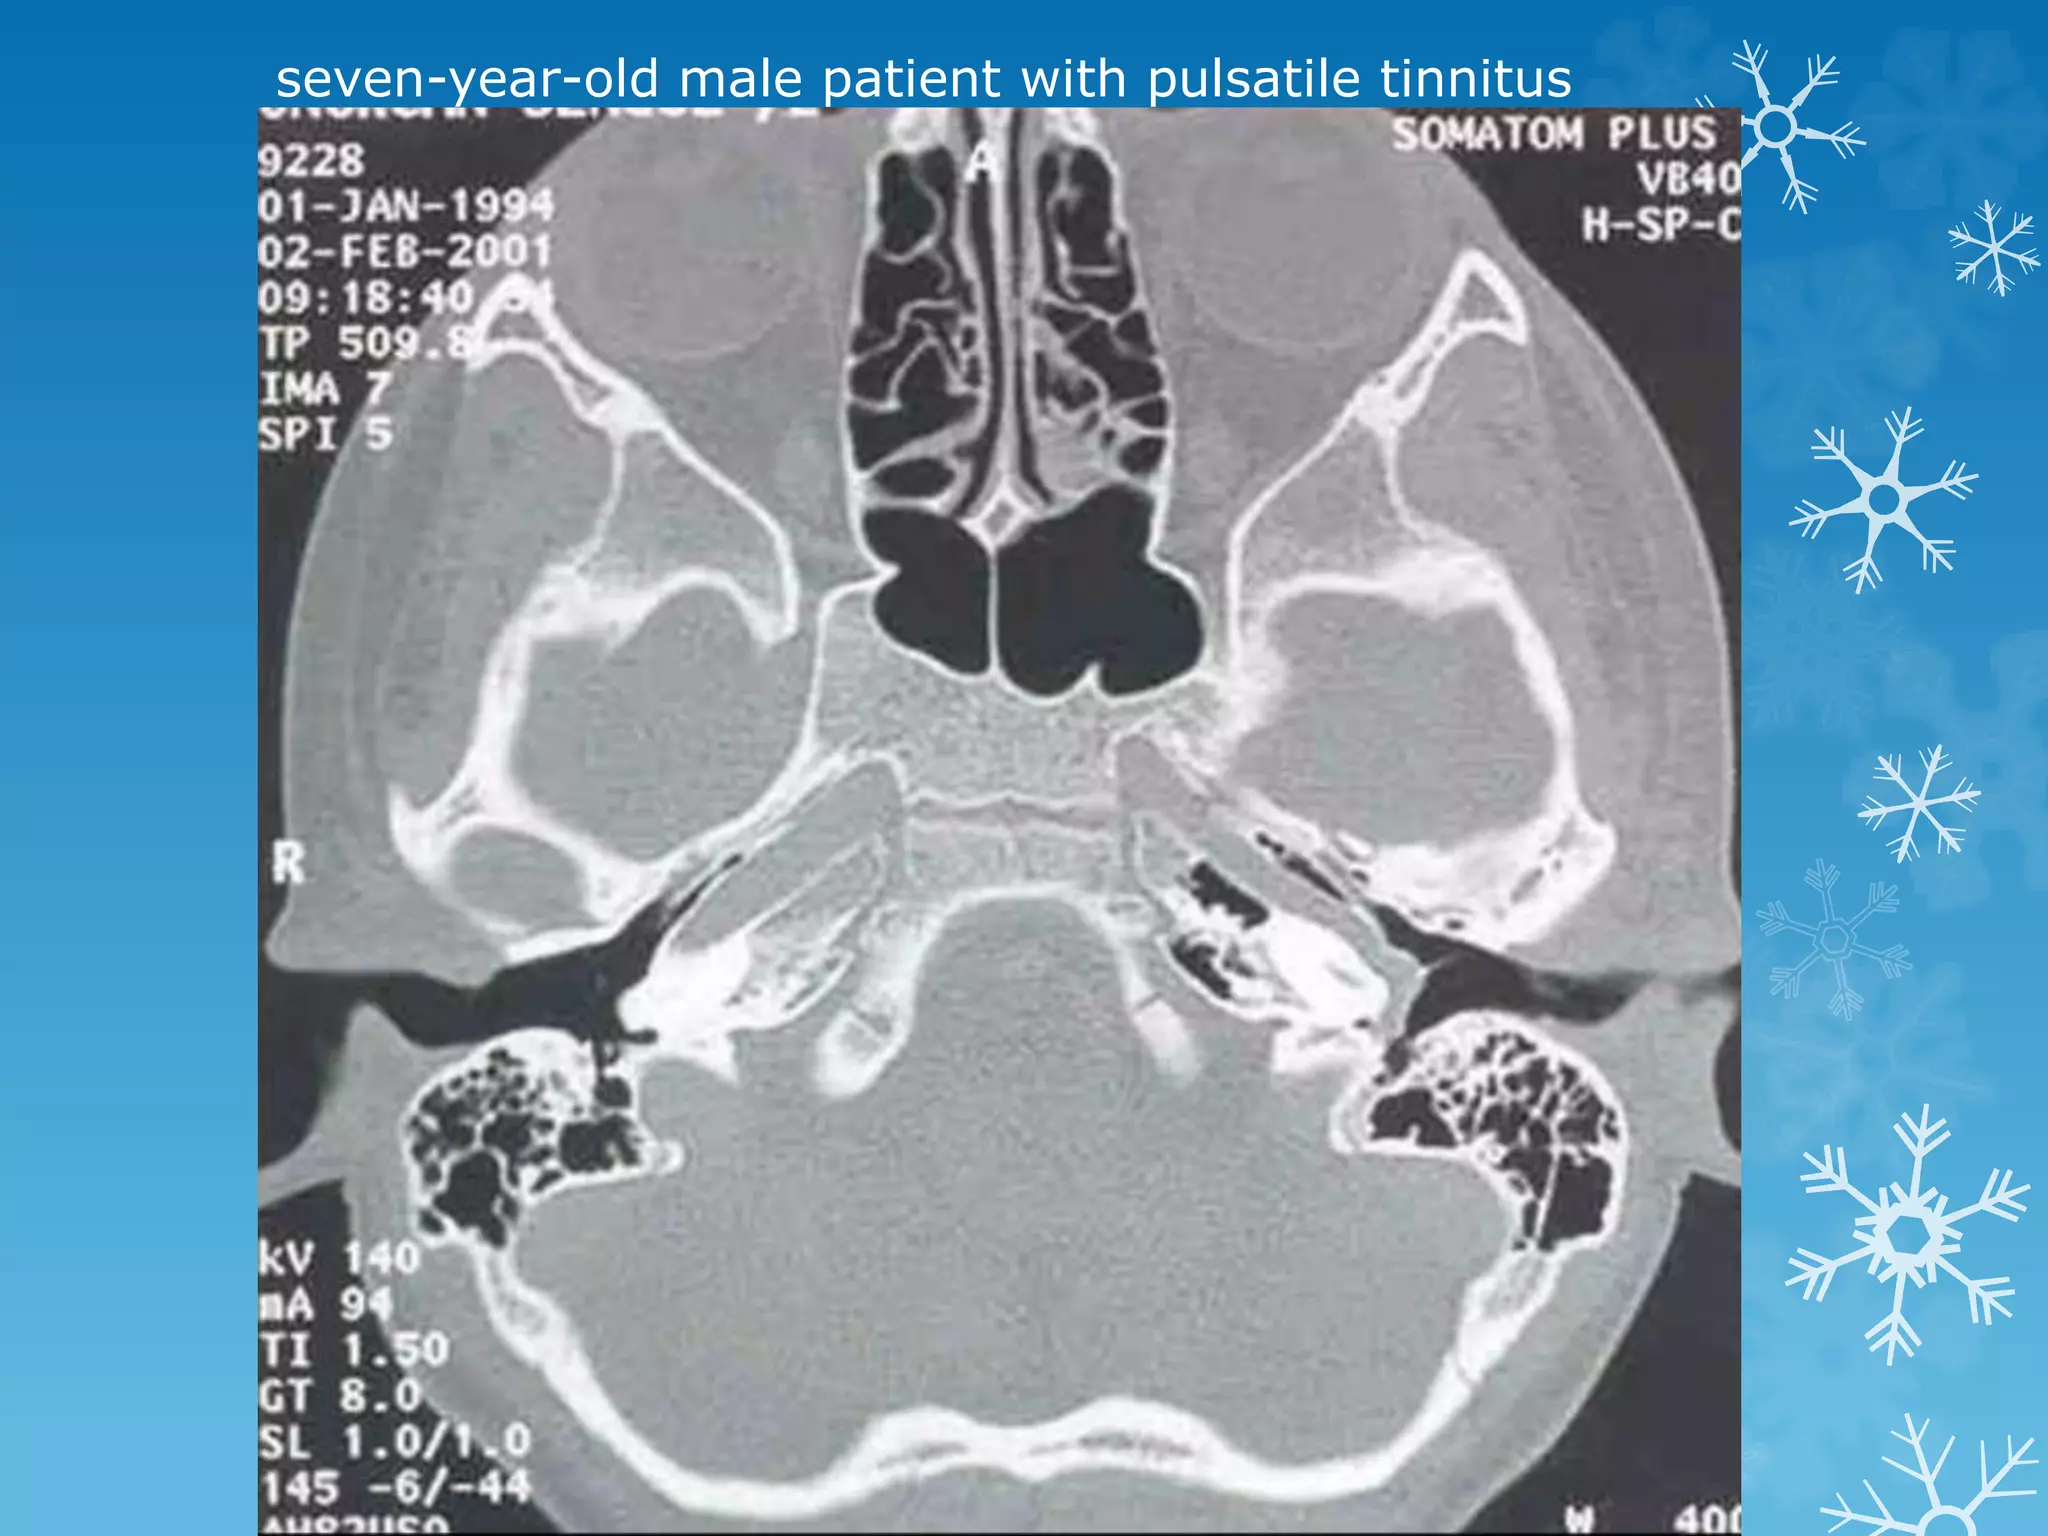

seven-year-old male patient with pulsatile tinnitus

Aberrant internal carotid artery

Some authors suggest that the reason could be the absence of the

hypotympanic bony plate because of a congenital failure of ossification.

With age, as the artery elongates and becomes tortuous, it protrudes

through the defect into the tympanic cavity.

Others suggest that the cervical ICA never develops and an aberrant carotid

artery forms when the inferior tympanic artery (a branch of the ascending

pharyngeal artery) enlarges to supply the territory of a cervical carotid

artery. The inferior tympanic artery runs through the middle ear and then

joins the horizontal petrous carotid artery. The so-called aberrant carotid

artery is, in fact, the markedly hypertrophied inferior tympanic artery.